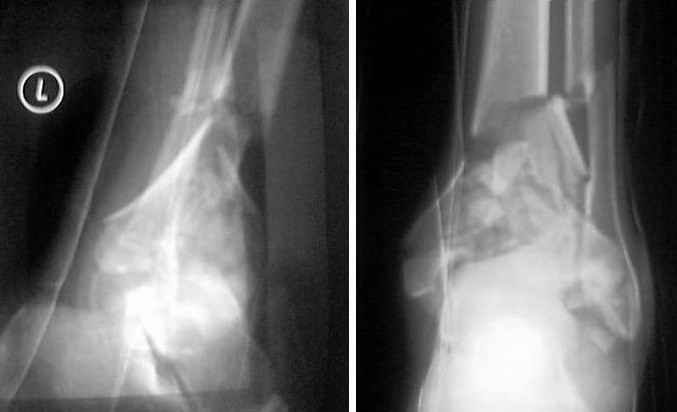

Dear all,40 y.o. man had sustained this terrible fracture falling from a motorbike.

Closed fracture.

This is really Pilon Fx (C3.3; the high energy and the extent of distal tibia comminution are defining it).

I would put simple unilateral, medially positioned external fixator (two pins in calcaneus - not to violate talus needed for later fusion, two in tibia), allow soft tissues to recover and in 2-3 weeks I would do delayed ankle fusion.

It is impossible to reconstruct the articular surface and even if somebody could do it, the cartilage will not be there/will not survive.

It is better to do it sooner (with minimal additional soft tissue damage) than later.

This is a pilon fracture. I suggest fixation of the fibula with a one-third tubular plate and a joint spanning external fixator on the medial side as initial treatment. If the tibial articular surface cannot be reconstituted, the patient will require an arthrodesis.